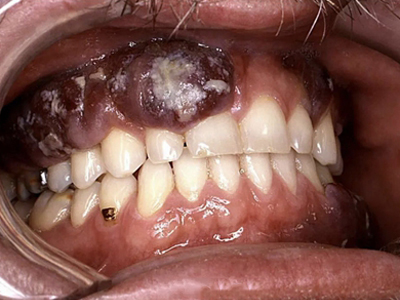

艾滋病皮肤肿瘤是由于艾滋病患者的人体免疫系统被破坏,造成人体免疫功能严重低下,从而引发各种肿瘤。在艾滋病皮肤肿瘤中,常见的有卡波西肉瘤、淋巴瘤、恶性黑色素瘤及鳞状细胞癌。

艾滋病可侵袭皮肤黏膜,引起卡波西肉瘤、淋巴瘤、恶性黑色素瘤及鳞状细胞癌等皮肤肿瘤,具体表现有所差异。

淋巴瘤引起的皮损无特异性,可为丘疹或结节,进展迅速时可融合成团,与周围组织粘连;恶性黑色素瘤通常形状不规则、不对称,颜色斑驳,直径可超过6mm或在短期内不断扩大,表面隆起粗糙不平。